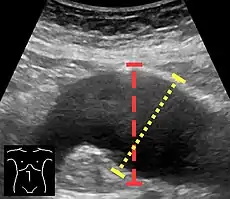

Aortic measurement on abdominal ultrasonography in the axial plane between the outer margins of the aortic wall.[33]

Ultrasonography in the sagittal plane, showing axial plane measure (dashed red line), as well as maximal diameter (dotted yellow line) which is preferred.